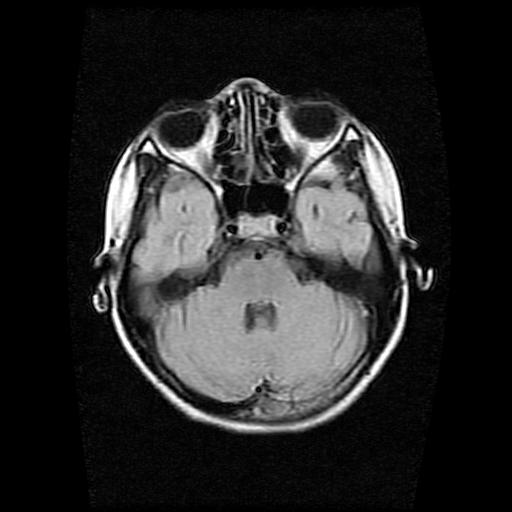

9岁女孩,三岁时诊断为癫痫,一直服丙戊酸钠,现患者一般情况良好,家长复查核磁片,看能否停药..

巨脑回